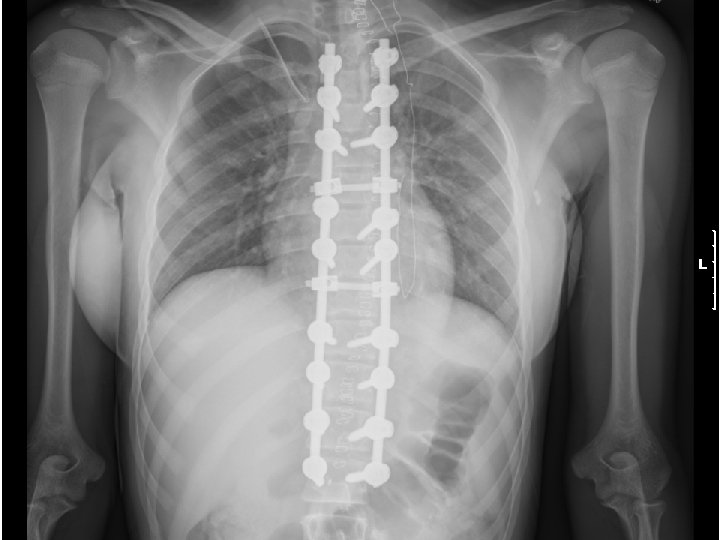

Idiopathic Scoliosis SURGICAL CORRECTION GOALS u. Reduce the magnitude of the curve u. Obtain fusion to prevent progression u. Create a well-balanced spine

Idiopathic Scoliosis • • • SURGICAL CORRECTION INDICATIONS Curves over 45 degrees Trunk deformity(rotation) Trunk balance Progressive curves despite bracing Congenital scoliosis Neurologic symptoms

Surgical Treatment for Scoliosis • Curves in growing children greater than 40 º require a spinal fusion (Risser grade 0 to 1 in girls and Risser 2 or 3 in boys) • Skeletally mature patients can be observed until their curves reach 50 º • Posterior spinal fusion is best choice for thoracic curves • Anterior spinal fusion is best treatment for thoracolumbar and lumbar curves

Surgical Treatment for Scoliosis